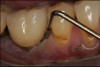

The entry of inflammatory cell infiltrate into the connective tissue (Figure 1 and Figure 2) differentiates peri-implantitis from peri-implant mucositis.1 Unlike a natural tooth—where periodontal fibers, transepithelial fibers, and gingival fibers absorb this exudate—none of these fibers are present around an implant (Figure 3). This allows the inflammatory cell exudate to directly enter the bone, resulting in bone loss and concomitant soft-tissue loss (Figure 4).1

Fig 2. Inflammatory cell exudate enters right into the bone.

Figure 2